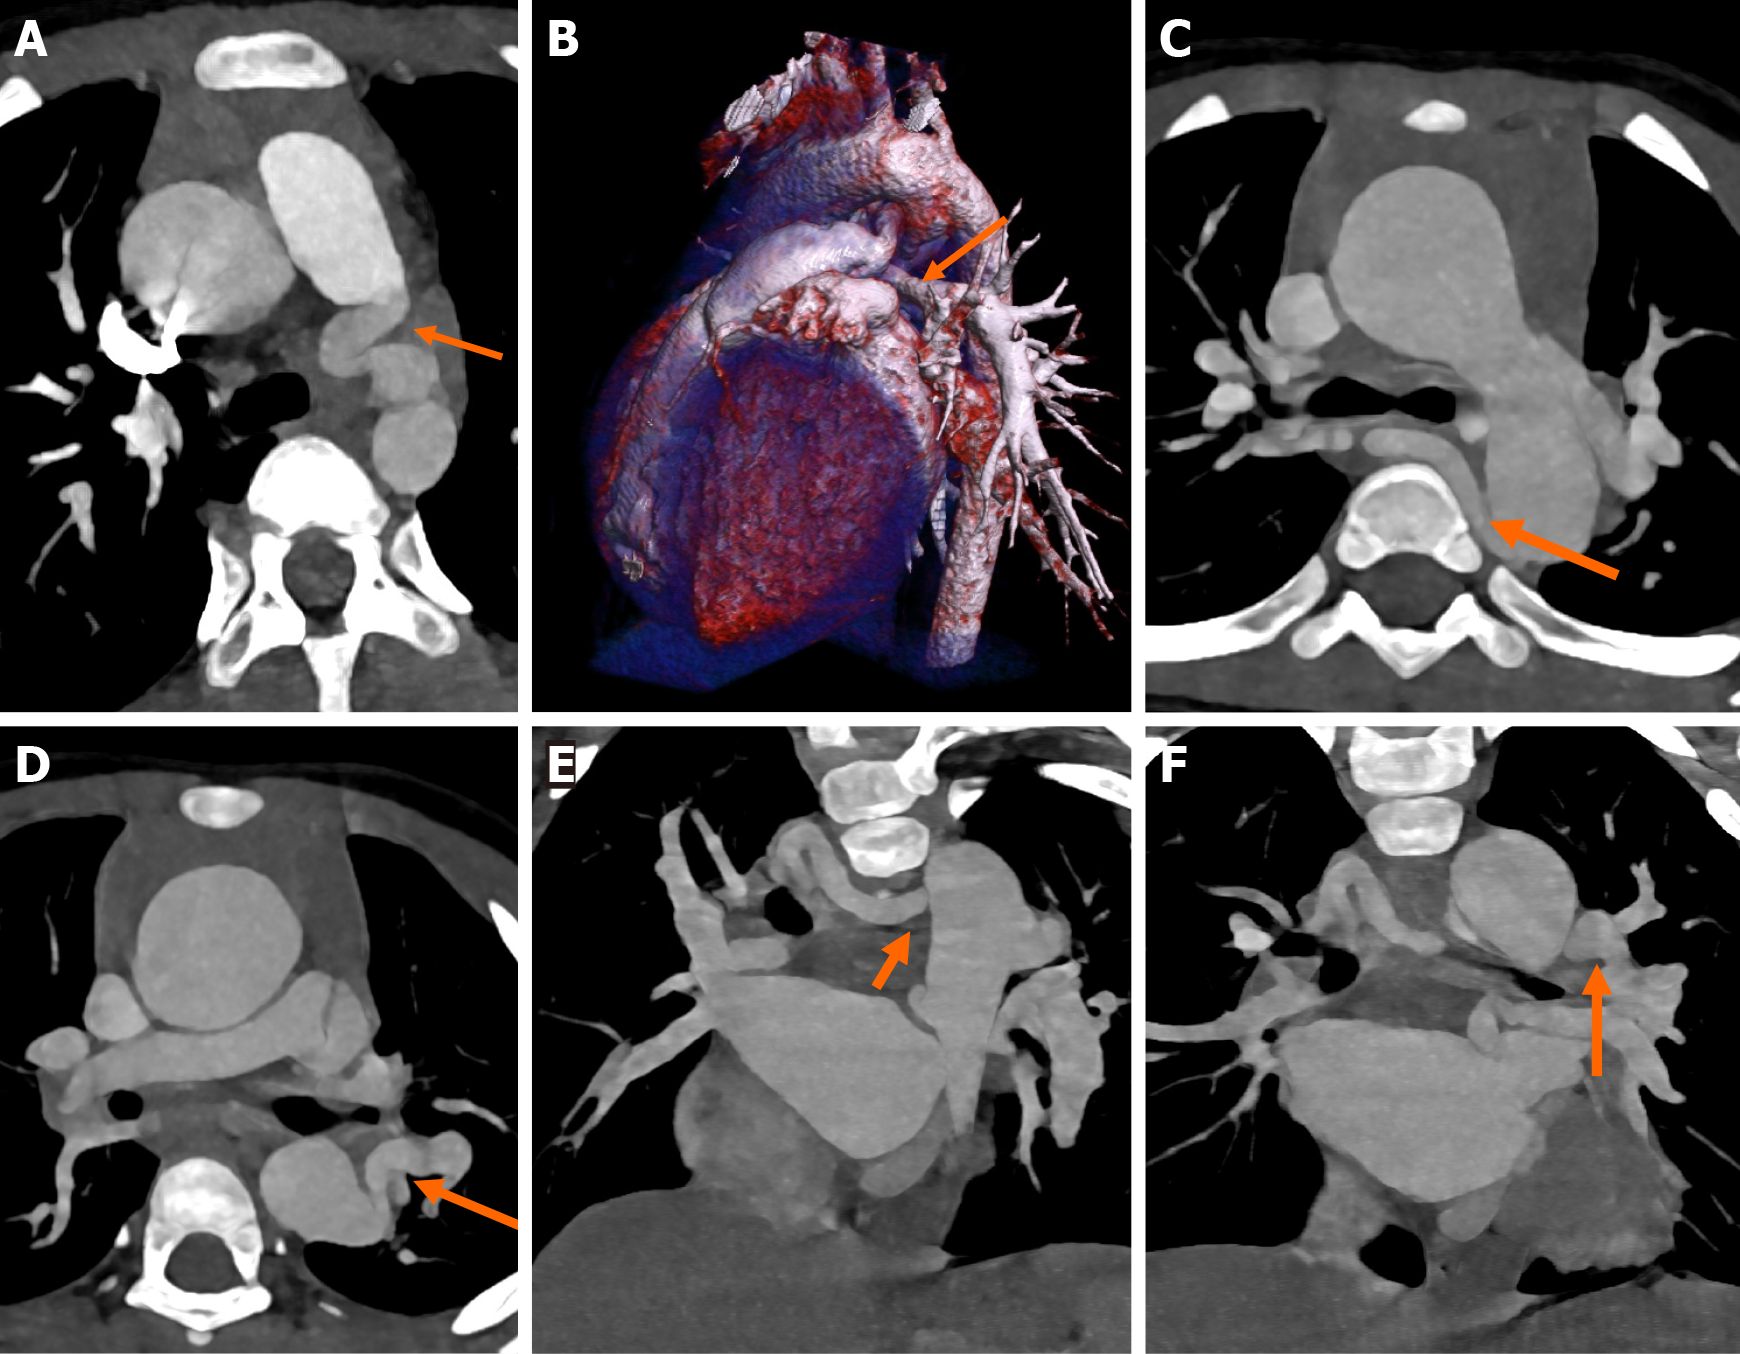

The classical components of TOF, including perimembranous VSD, aortic override, pulmonary stenosis/atresia, and consequent right RVH, are very well delineated on CT (Figure 5A-C). The aortic override in TOF is typically less than or equal to 50%, in TOF. The degree of RVOTO is variable. Pulmonary stenosis may be infundibular, valvular, or supravalvular. Isolated left PA stenosis is the most common (Figure 5D-F). Rarely, stenosis of the branch PA may be coexistent with main PA stenosis (Figure 6A-D)[37]. In cases with pulmonary atresia, the main PA is atretic, and the branch pulmonary arteries may be confluent or isolated (Figure 6E-G). The PV may be absent in 3%-6% cases and is characterized by an aneurysmal main PA (Figure 6H)[38].

Figure 5 Computed tomography images. A-C: Axial (A and B) and sagittal reformatted images (C) of computed tomography angiography in a child with cyanosis, showing infundibular pulmonary stenosis (block arrow in A), right ventricular hypertrophy (asterisk in B), perimembranous ventricular septal defect (block arrow in B) with 50% aortic override (asterisk in C) consistent with classical tetralogy of Fallot; D-F: Axial (D and E) images showing stenosis at the origin of the left pulmonary artery (arrow). The right pulmonary artery was normal (asterisk); F: Three-dimensional volume rendered image showing the left pulmonary artery stenosis (arrow).

Figure 6

Figure 6 Computed tomography images. A-D: Oblique axial maximum intensity projection images and volume rendered image showing supravalvular main pulmonary artery (orange arrow) and right pulmonary artery (blue arrow) stenosis in a known case of TOF (A); coronal reformat image showing the main pulmonary artery stenosis (arrow) (B); coronal reformat image showing right pulmonary artery stenosis (blue arrow) (C); three-dimensional volume rendered image showing supravalvular main pulmonary artery stenosis (arrow) (D); E-H: Axial computed tomography angiography images showing pulmonary arterial anomalies in different patients of tetralogy of Fallot. E: Pulmonary atresia (block arrow) with reformed, confluent pulmonary arteries (asterisk); F: Pulmonary atresia with non-confluent, reformed pulmonary arteries (block arrow); G: Pulmonary atresia with absent main and branch pulmonary arteries (block arrow); H: Aneurysmal dilatation of the main pulmonary artery (block arrow) due to absent pulmonary valve.